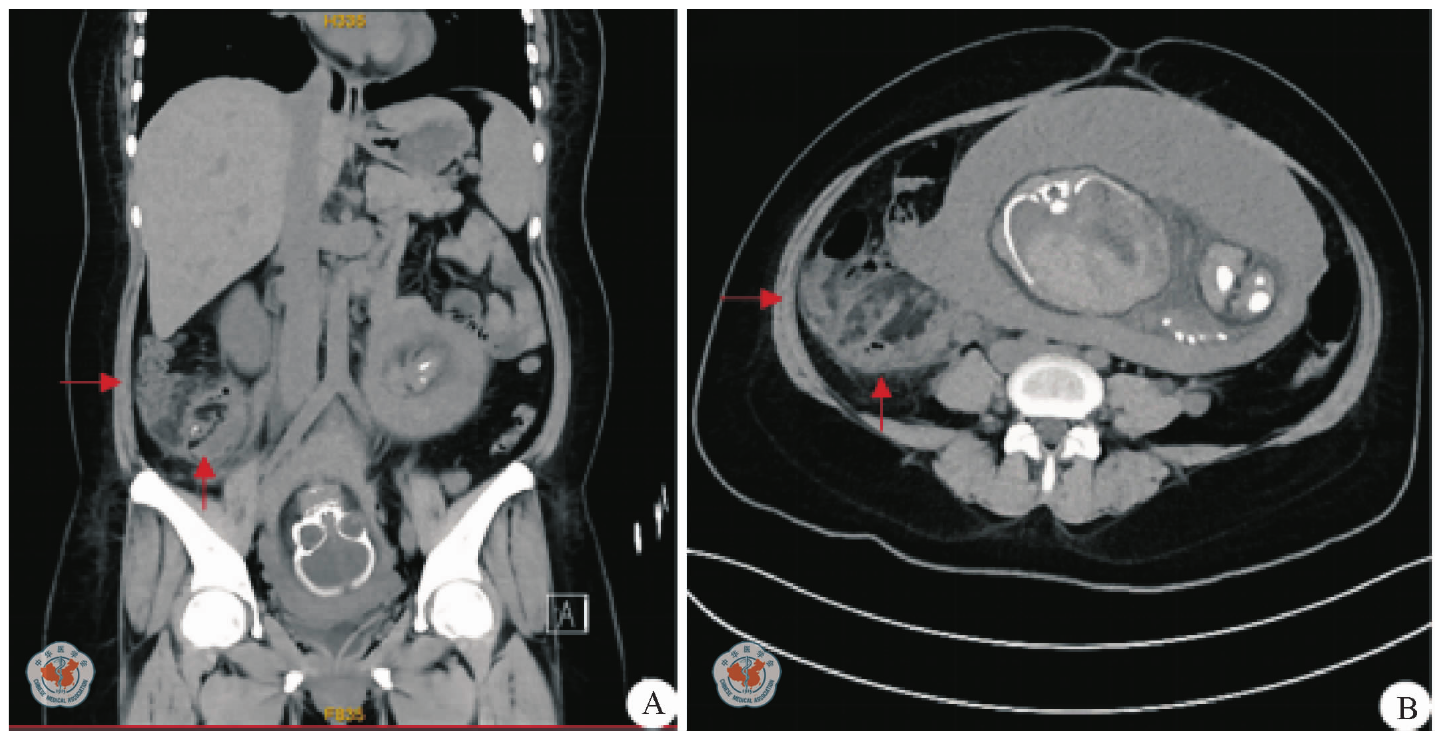

图2 妊娠合并坏疽性阑尾炎致感染性休克患者2021年9月15日(孕30+6周)腹部CT图。A:矢状面,B:横断面(箭头所示为化脓阑尾及周围渗出)